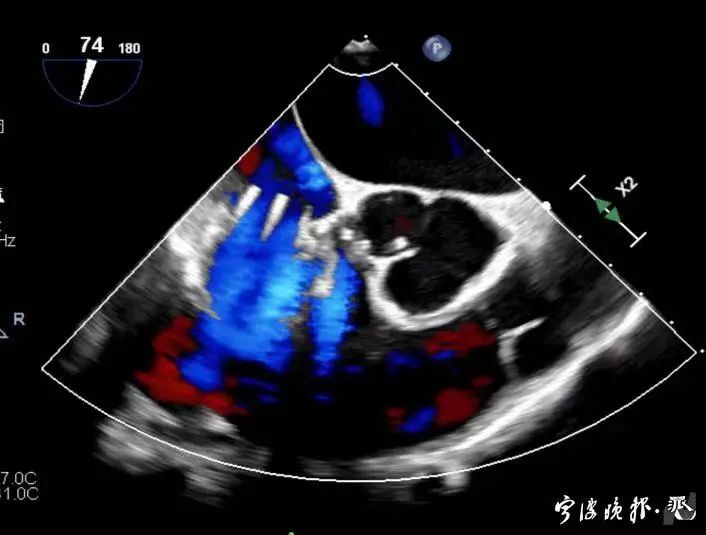

術(shù)后食道心超示三尖瓣反流消失